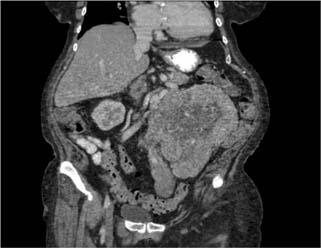

A 72-year-old female presented to her primary care physician reporting progressive fatigue, abdominal pain, and a 35-pound unintentional weight loss. She was noted to have a palpable left abdominal mass, and laboratory work was notable for hypercalcemia, thrombocytosis, and elevated alkaline phosphatase. Subsequent computed tomography (CT) imaging revealed a 16-cm left-sided renal mass with caudal tumor extension and bulky regional lymphadenopathy along the left gonadal vein (Figure 1). The patient was then referred to our urology department for further management.

Figure 1: Coronal view of computed tomography of abdomen/pelvis revealing a large left renal mass with direct extension into the left gonadal vein.